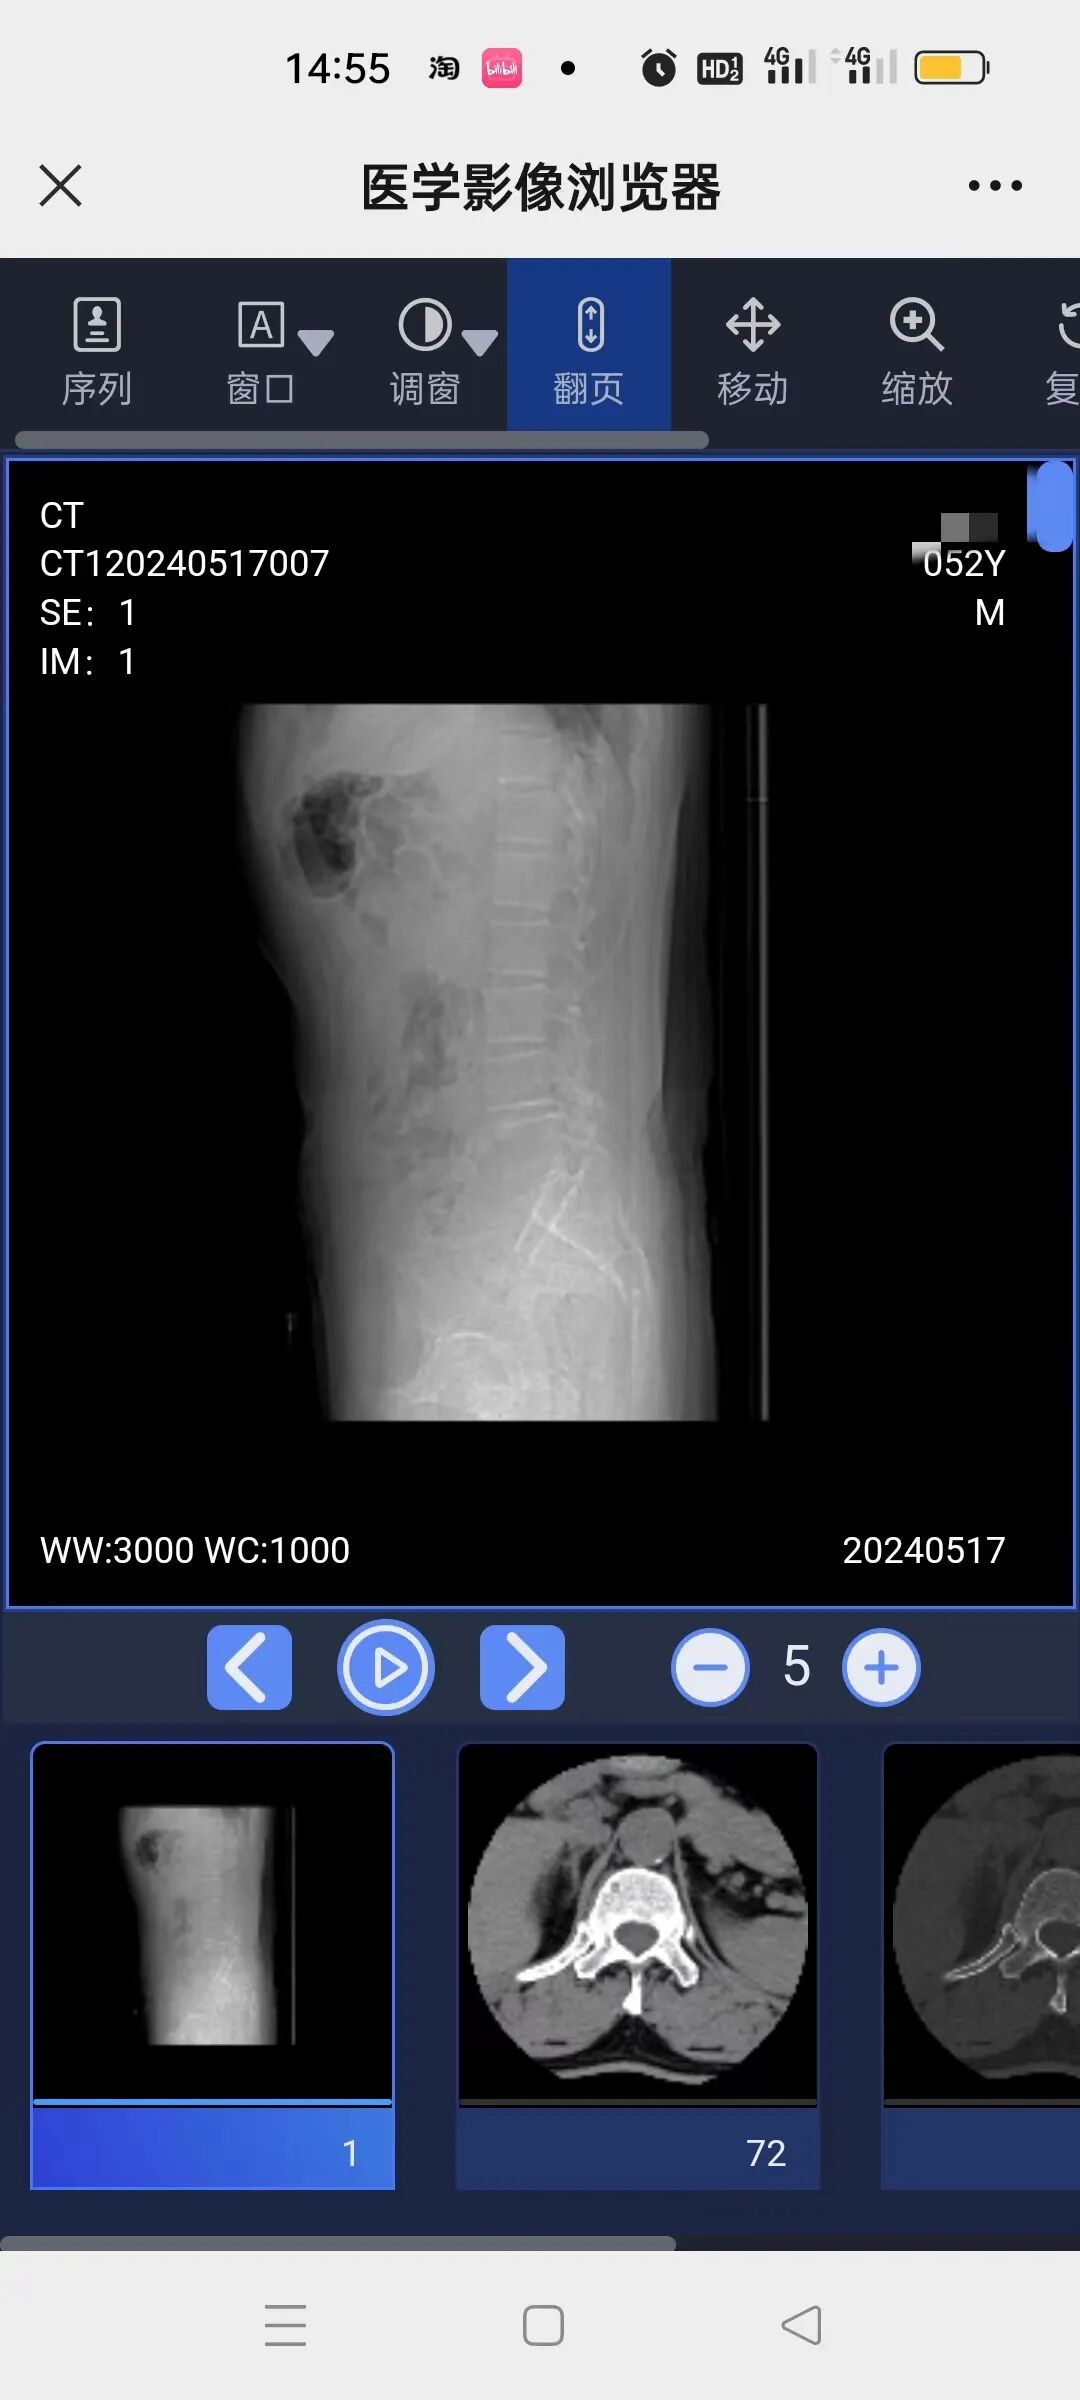

与传统“大袋子+塑料胶片”模式不同的是,云胶片不依赖于胶片介质,它是通过数字化存储、网络化运输,将医学影像信息存储在云端服务器上的电子胶片。云胶片保存患者全部检查报告和原始高清DICOM图像,支持放大、缩小、窗宽窗位、测量,具备丰富的图像后处理功能。尤其是当患者需要跨院就医时,传统胶片提供的只是部分影像数据,管理不当还可能出现胶片磨损、老化、丢失等情况,难以二次利用。而应用云胶片,患者只需保存二维码,在远程会诊或者跨院就医时直接分享给医生,便可即时调阅影像资料,协助医生诊断治疗,有效减少不必要的重复检查,看病就医更加便捷省心。

在我院做完影像检查后,无需打印实体胶片,医生及就诊患者通过电脑端或扫描纸质报告单和胶片袋上的二维码,便能随时随地在线调阅检查报告和医学图像。

传统胶片是从拍摄的多张影像中,挑选几张打印出来,而数字云影像提供完整的原始DICOM数据查询,比传统胶片的信息量更完整、精确。并可以在手机、电脑上将图片自由放大,方便医生进行各种测量,看得更细致,提高诊断质量。